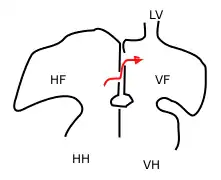

L'atrium droit reçoit la grande majorité du retour veineux. Celui-ci est constitué par deux courants, l'un issu de la veine ombilicale et du placenta (riche en oxygène), l'autre venant de la partie haute du corps et du cerveau par la veine cave supérieure (appauvri en oxygène). Grâce à la présence de la valve de Vieussens au pied de la veine cave inférieure et à celle du foramen ovale, ces deux flux suivent des circuits préférentiels différents et ne se mélangent que faiblement :

- Le sang oxygéné provenant du placenta se dirige préférentiellement au travers du foramen ovale vers la circulation cérébrale (via l'atrium gauche, le ventricule gauche et l'aorte ascendante) ;

- Le sang moins oxygéné revenant de la partie supérieure du corps par la veine cave supérieure est dirigé préférentiellement vers l'orifice tricuspide, le ventricule droit, l'artère pulmonaire, et de là rejoint le placenta via le canal artériel, l'aorte descendante et les artères ombilicales.

Ainsi, le sang le plus oxygéné est destiné en priorité au cerveau.